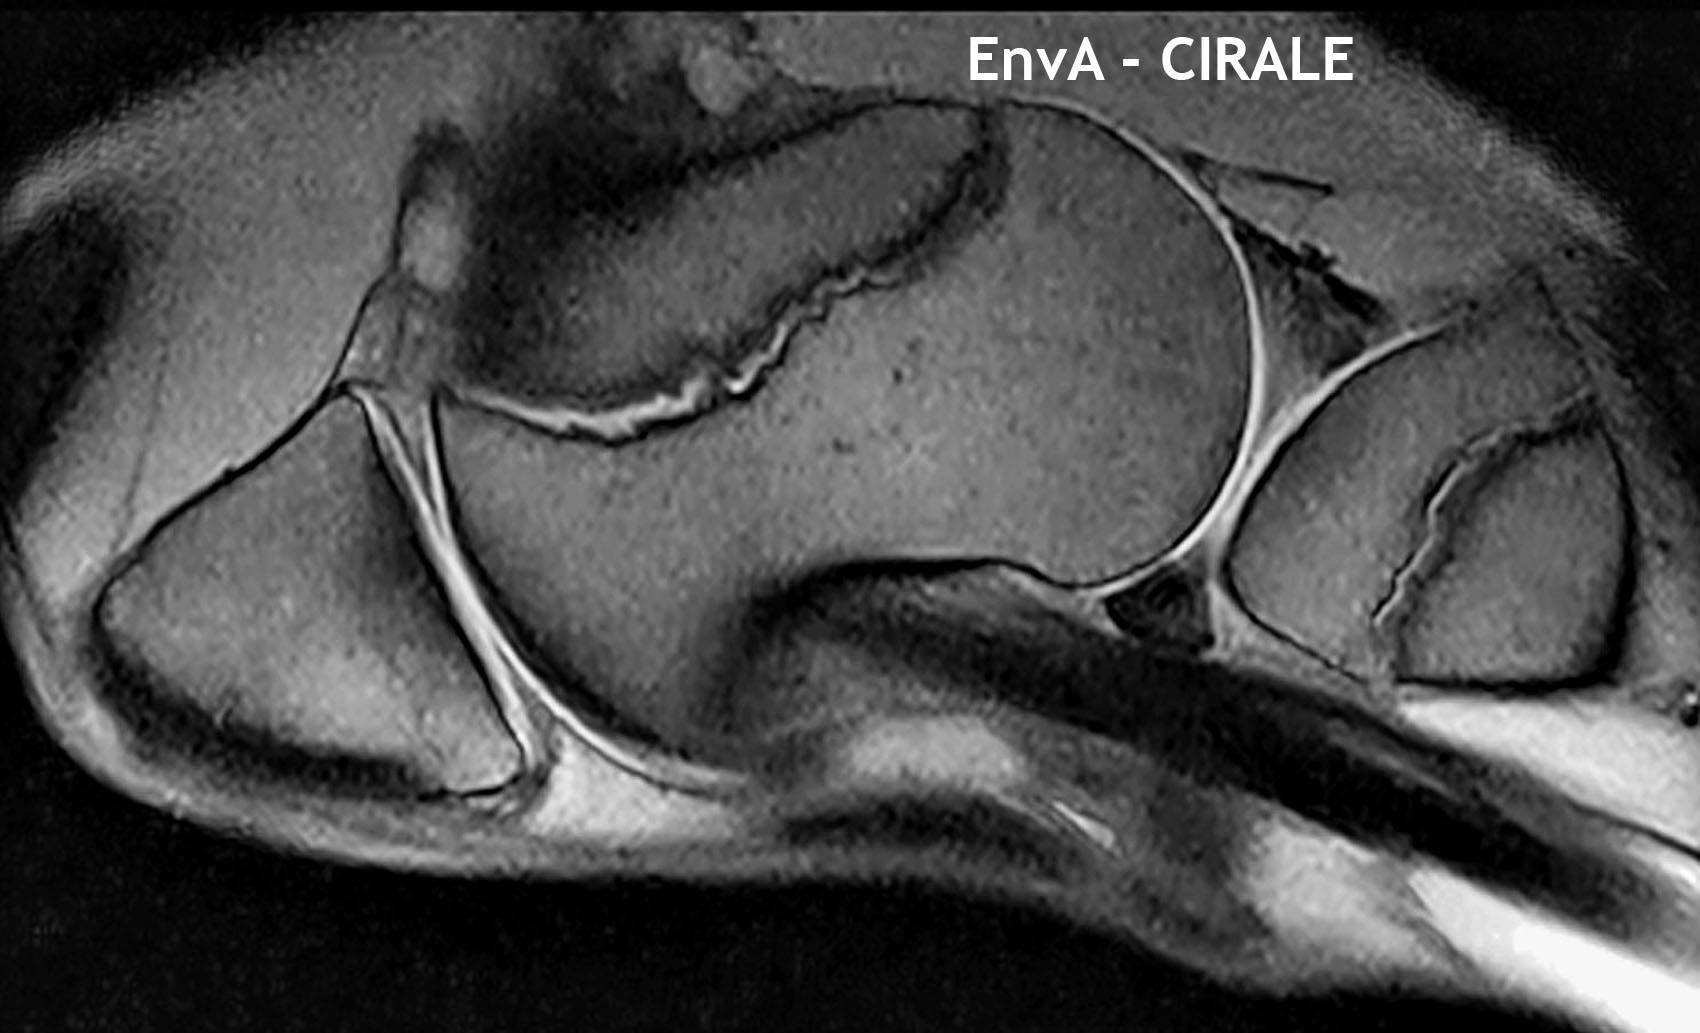

А помните, я упоминала про мою очередную поездку в ветшколу/клинику CIRALE ? Вот их новый ИРМ

Причем все не особо дорого, потому что работают студенты и ветеринары-стажеры по базовым манипуляциям, и часть расходов клиники покрывается программами Евросоюза и французским фондом EPERON (распределяющим в год 10 млн евро на инновации в конной отрасли, откуда деньги ? - с тотализатора). Лошадей туда везут со всей Европы, аж со Скандинавии. Особая слава у CIRALE - это диагностика проблем локомоторного аппарата, другими словами - проблемы всего, что влияет на движения (суставы, сухожильно-связочный, позвоночник, повреждения мягких тканей и тп).